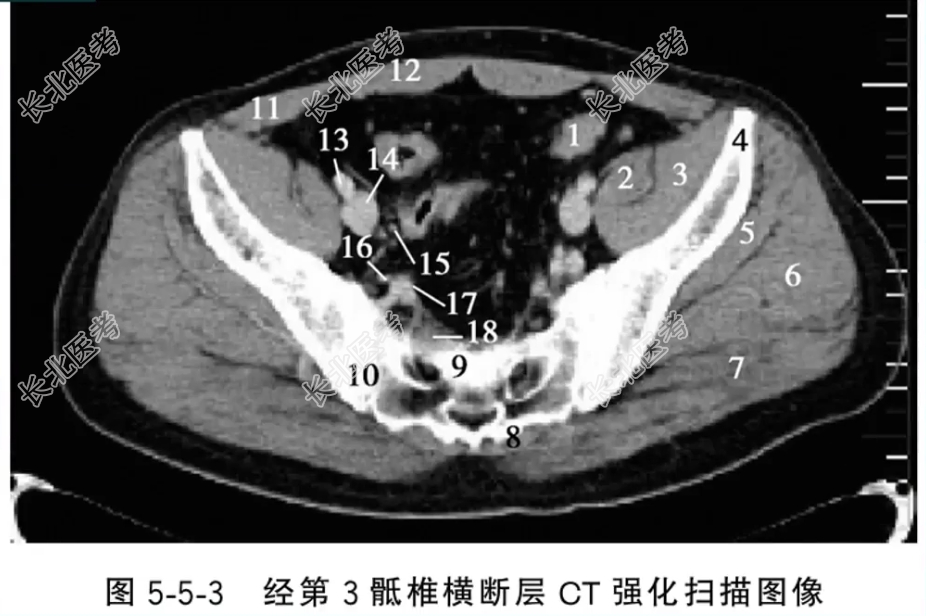

- 单项选择题经第3骶椎横断层CT强化扫描图像中,标记为15的结构是什么

A、乙状结肠

B、输尿管

C、右髂内动脉

D、右髂外动脉

E、腰大肌